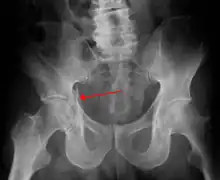

| Acetabular fracture as seen on plain X-ray |

Fractures of the acetabulum occur when the head of the femur is driven into the pelvis. This injury is caused by a blow to either the side or front of the knee and often occurs as a dashboard injury accompanied by a fracture of the femur.[1]

The acetabulum is a cavity situated on the outer surface of the hip bone, also called the coxal bone or innominate bone. It is made up of three bones, the ilium, ischium, and pubis. Together, the acetabulum and the head of the femur form the hip joint.